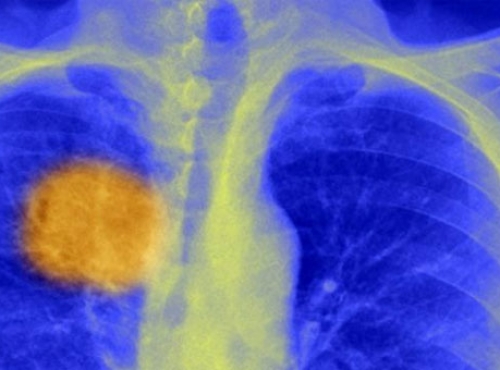

Раковая опухоль – это не единое, равномерное образование. Она состоит из совершенно разных, по-разному мутировавших клеток, поэтому и вести себя отдельные участки опухоли могут по-разному.